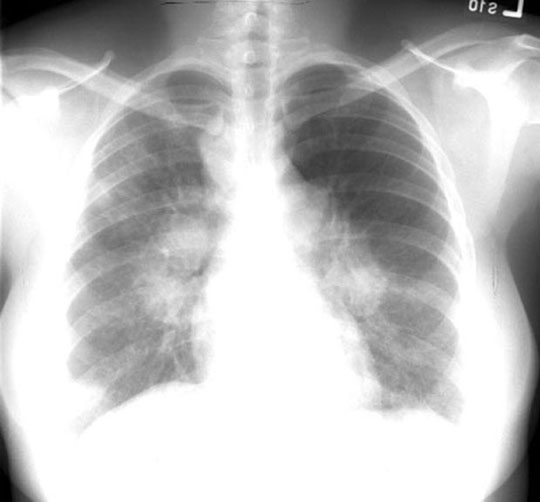

32 year old female referred because of abnormal chest x-ray detected during a routine pre employment screening. History of Bell's palsy 2 years back.

Findings:

• Lymph nodes

• Bilateral symmetrical hilar nodes

• Potato nodes

• Mediastinal nodes (not in anterior mediastinum)

• Alveolar infiltrates

Diagnosis

Sarcoidosis